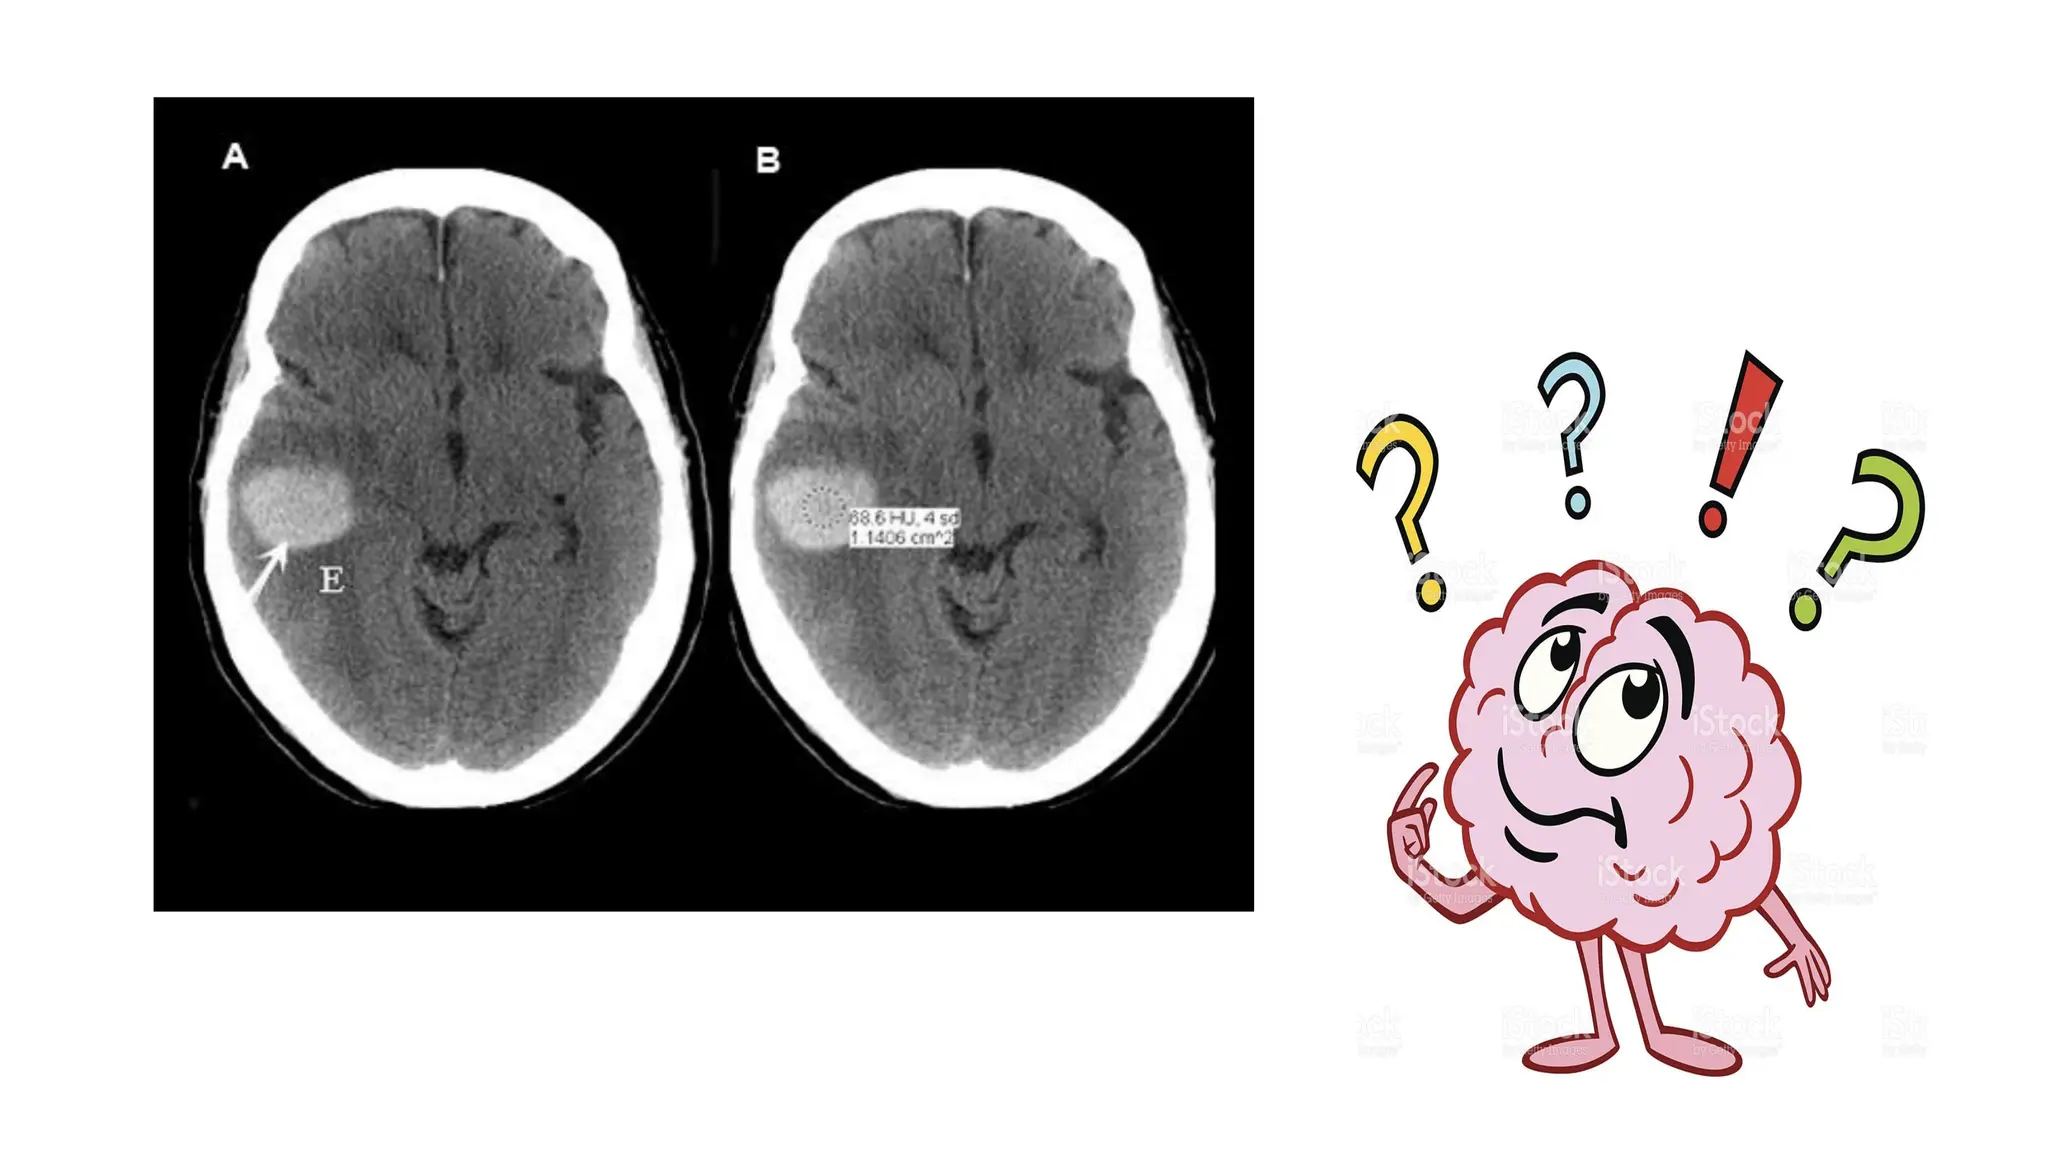

• Always describe CT findings as densities- isodense/hypodense/hyperdense.

• Higher the density = whiter the appearance

• Lower the density = darker the appearance

• Higher density than brain-hyperdense ( skull is the best example)

• Anything darker (lower density) than brain= hypodense( CSF and air are

classical examples)

ISCHAEMIC STROKE

INTRACRANIAL HEMORRHAGE